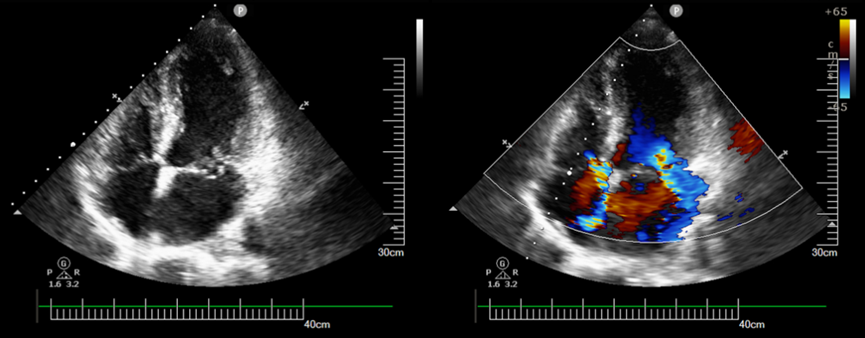

患者是一位年长男性,因突发胸闷胸痛、气喘、大汗淋漓经120急救送至我院,急查心电图提示患者急性心肌梗死,且床旁心超提示存在二尖瓣脱垂伴重度反流。

心超显示二尖瓣脱垂、反流明显